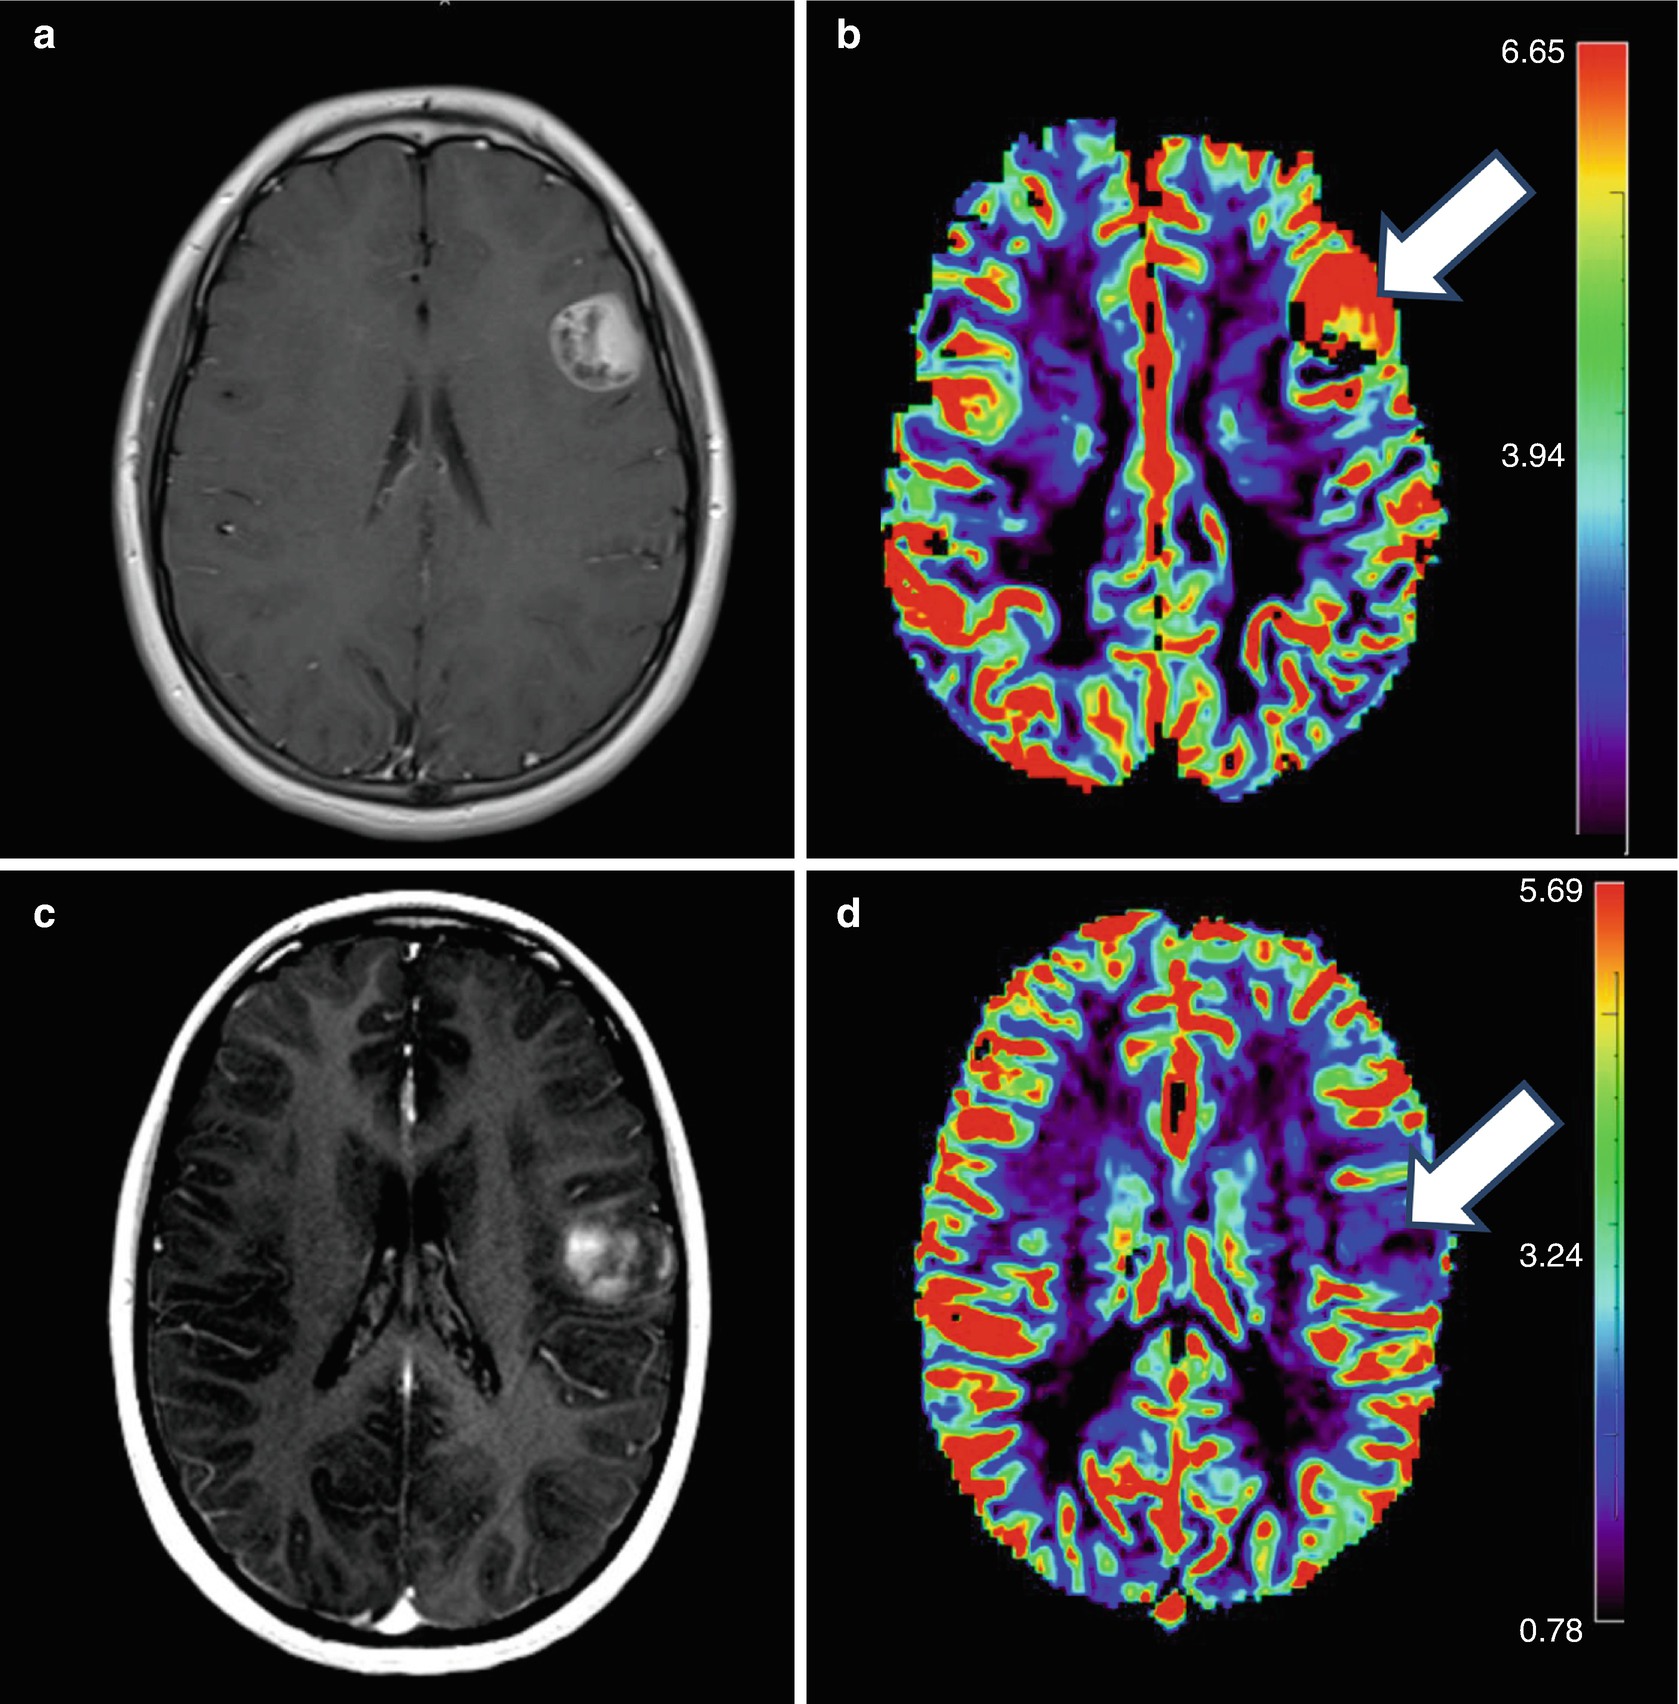

Glioblastoma Multiforme Who Grade 4 Patient 2 A An Anaplastic Download Scientific Diagram